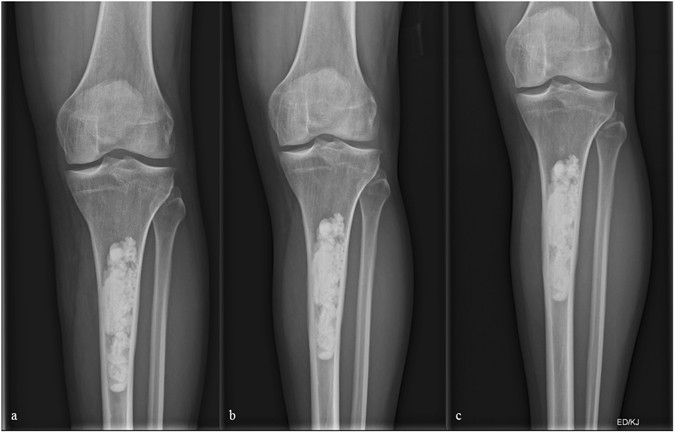

Figure 1

(a–c) X-ray of a 36 year-old male patient few days following curettage of a low-grade chondrosarcoma of the left proximal tibia. (b and c) Follow-up radiographs 7 and 13 months following index surgery showing integration but no resorption of the artificial bone graft substitute.